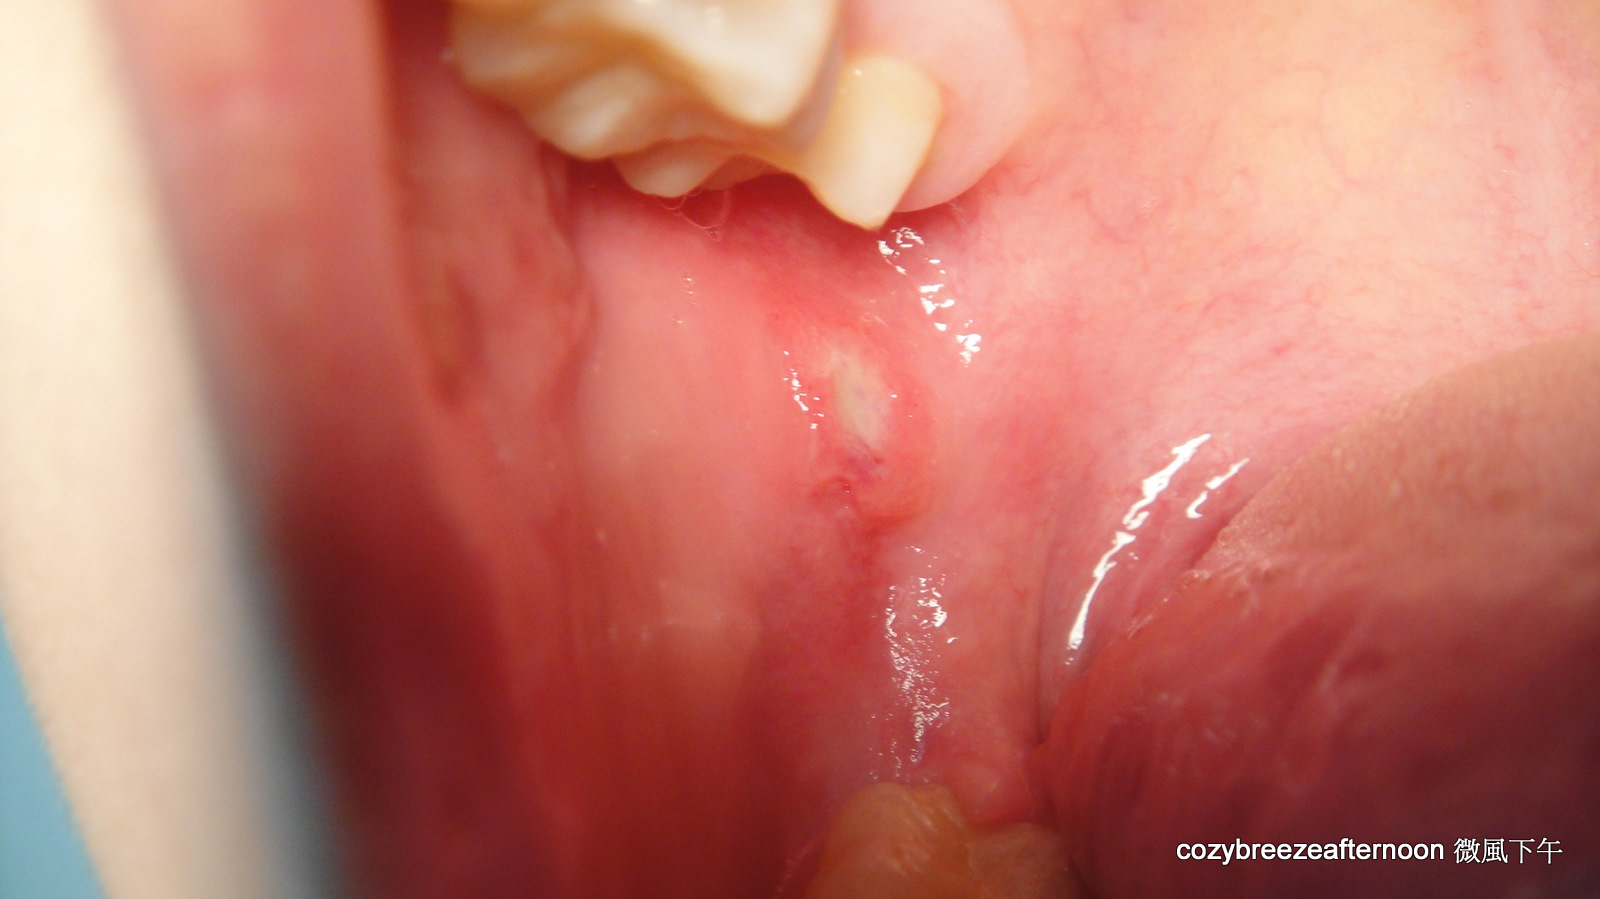

復發性口腔潰瘍是一種相當常見口腔黏膜疾病,一年中每個月至少要有一次的口腔黏膜潰瘍,才算是典型的復發性口腔潰瘍,口腔潰瘍之個數可能一個或多個,通常發生於非角化、可動性口腔黏膜如頰黏膜、唇黏膜、舌腹黏膜等,急性期疼痛明顯,至慢性期疼痛會緩解。

在台灣的發生率約10.5%,臨床上復發性口腔潰瘍有三種型態,小型、大型、泡疹型。小型的復發性口腔潰瘍為1公分以下,潰瘍約7至14天會復原,小型的復發性口腔潰瘍雖然很小,但有時相當的疼痛。大型的復發性口腔潰瘍直徑約1-3公分,通常要2-6個星期才會癒合,且可能會結痂,大型的復發性口腔潰瘍好發於唇黏膜、軟顎等處。泡疹型復發性口腔潰瘍,數目很多,集結成團,且常復發,每個潰瘍直徑約1-3 mm,有時多個小潰瘍會集結起來成為大潰瘍,泡疹型復發性口腔潰瘍約7-10天會痊癒,通常從成人期開始發生,且好發於女性患者。

1. 復發性口瘡性口腔炎(recurrent aphthous stomatitis, RAS或RAU,canker sore)

RAS平均佔一般人口約20﹪,因為人種及社經地位的差異,範圍從5-50﹪不等,小孩的盛行率約39﹪,如果父母親都是RAS患者,則高達90﹪會發生RAS;如果是高社經的小孩,比一般小孩超出5倍的盛行率,陸續研究指出學生時期的壓力是發生RSA的重要因子, 原因不明,一般醫師會跟病人說是火氣大、睡眠不足。